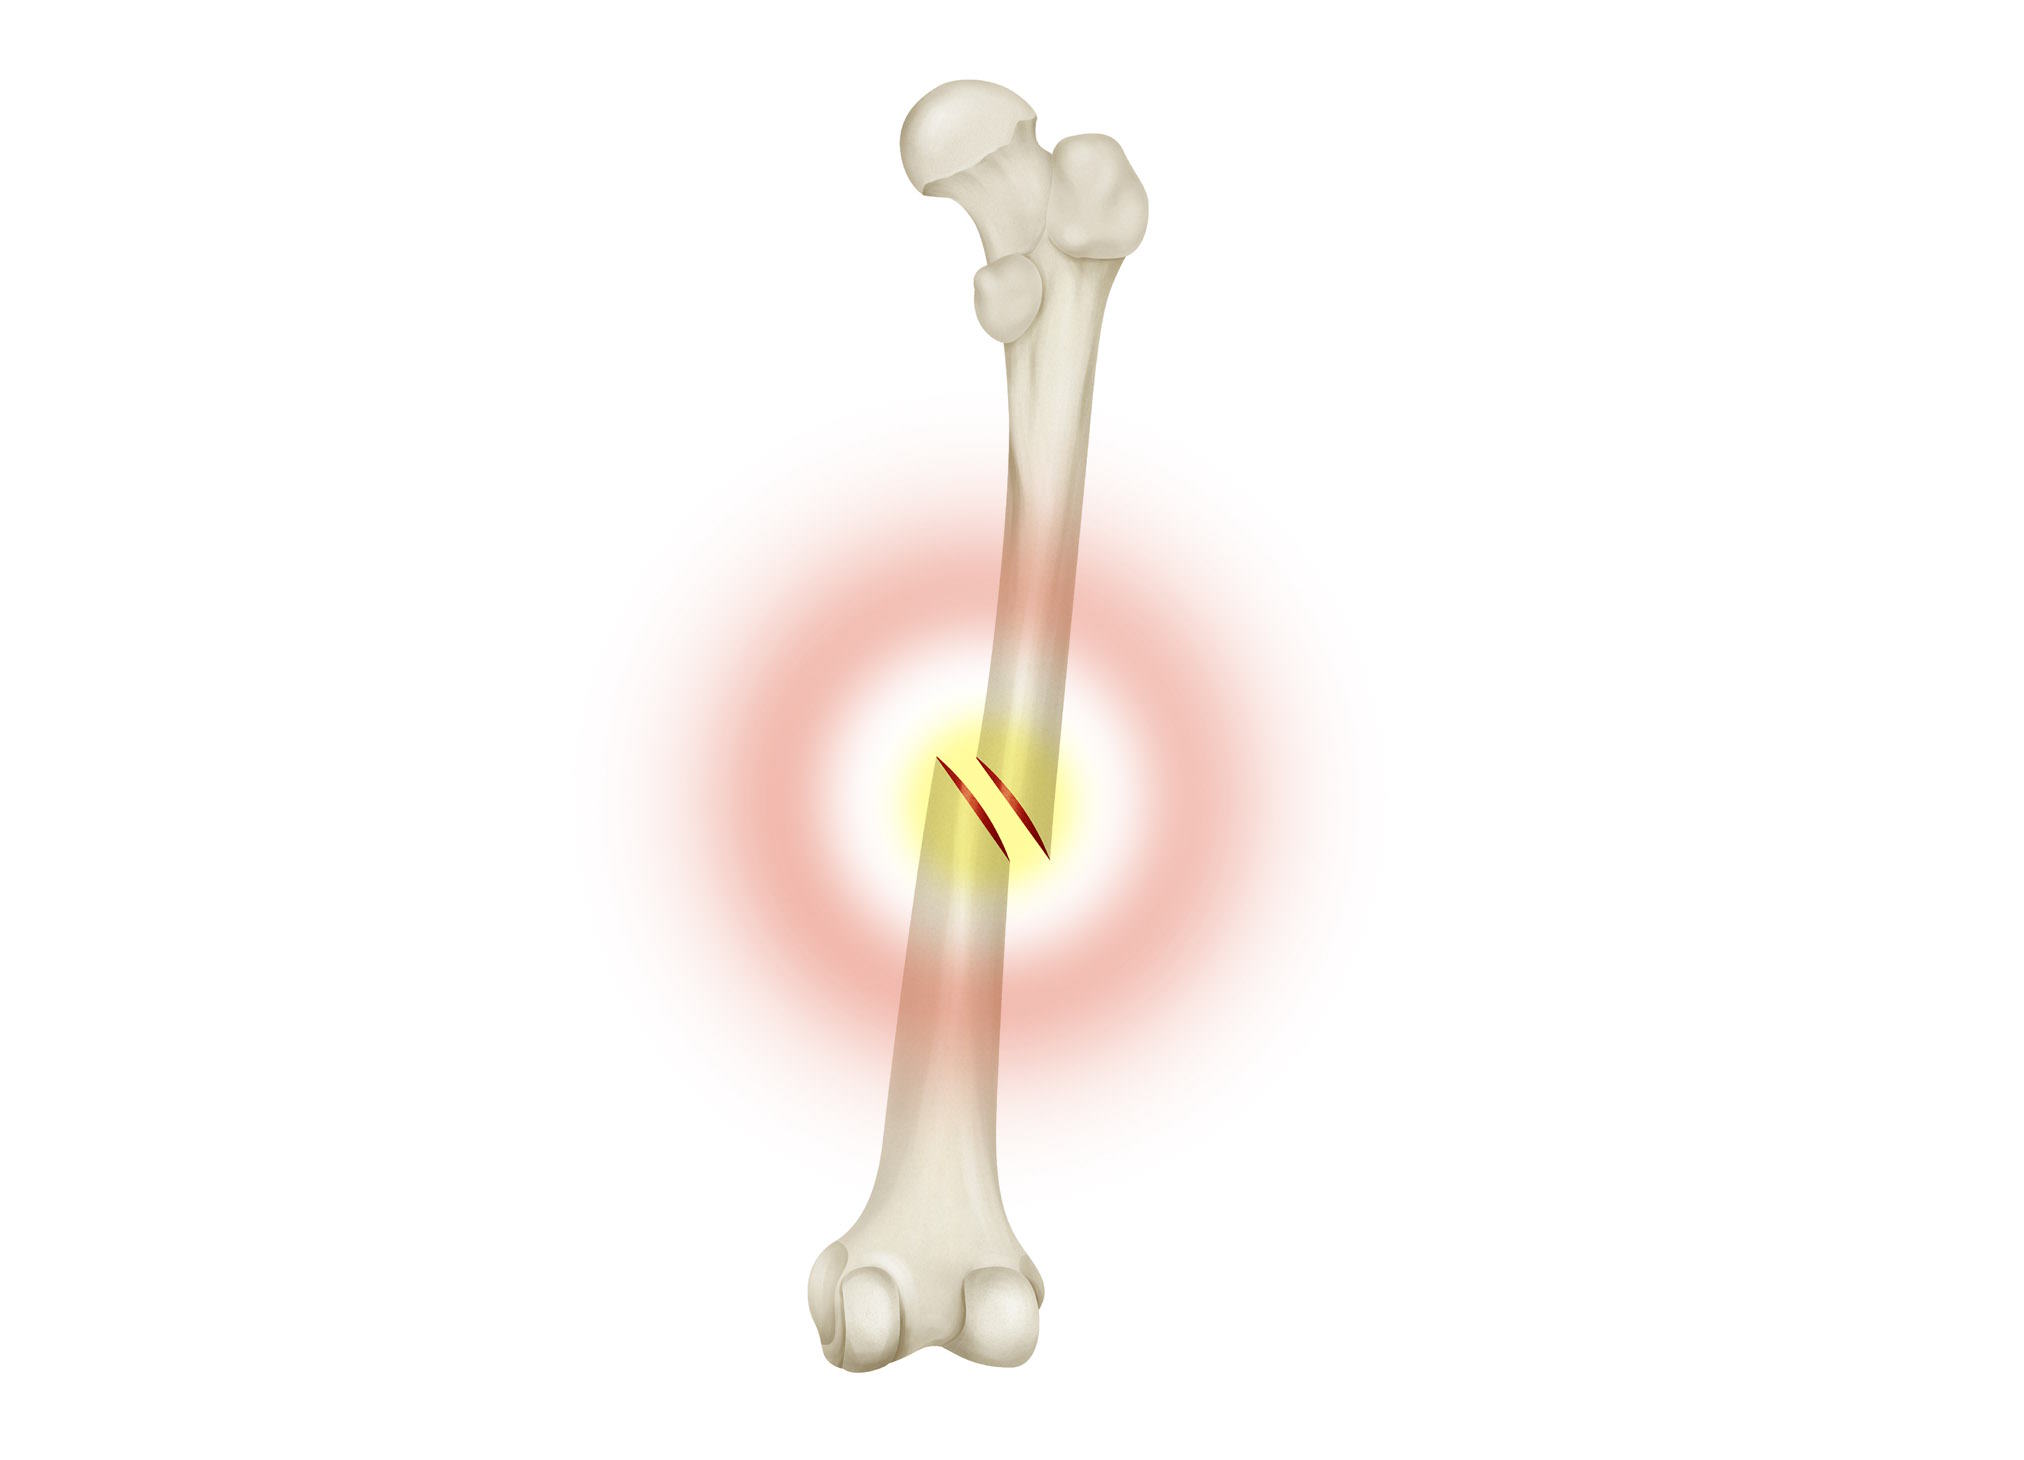

¿Qué son las Fracturas de Hueso? Definición y tipos

Fractura es la rotura parcial o total de un hueso, la pérdida de continuidad normal de la sustancia ósea o cartilaginosa. La consecuencia de golpes, fuerzas o tracciones cuya intensidad supera la elasticidad del hueso. Se denomina así a todo tipo de roturas, tanto las microscópicas como aquellas en las que se destruye parte del hueso.

Tipos de Fracturas de Hueso

La denominación de los tipos de rotura son consecuencia de la repetición. Hay roturas que se dan con más frecuencia que otras, por ello, se han diseñado unos patrones que, aunque varíen dependiendo de la zona corporal afectada, el hueso afectado y otros factores asociados, ayudan a acertar con su tratamiento.

De esta manera, el protocolo de fisioterapia que aplicaremos en consulta se adaptará a la fractura que presente el paciente. Así, podemos llevar a cabo rehabilitación de fractura de tibia y peroné, fisioterapia para fractura de pelvis, clavícula, etc.

Se pueden clasificar:

- Según su etiología, por ejemplo Fracturas Traumáticas, Patológicas o por Fatiga de marcha o estrés.

- Según su exposición, en forma de Fractura Abierta o Cerrada.

- Según la ubicación en el hueso, Fractura Epifisiaria, Diafisiaria, Metafisiaria.

- Según el tipo de fractura, Fractura en pico de plancha, Conminuta, Lineal, Oblicua, Transversal, Espiral, Segmentaria, de Compresión, Impactada, Deprimida, en Tallo Verde, en Botón o Torus, y por último Deformación Plástica.

El conocimiento del tipo de fractura y la valoración en consulta nos permitirá aplicar el tratamiento de fisioterapia más adecuado para lograr la completa recuperación.